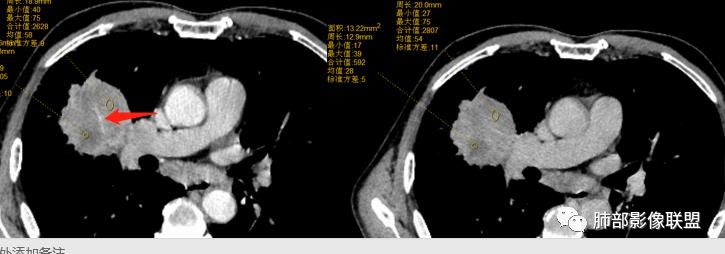

对,有血管走形

这个血管在病灶中间走行。鳞癌不会这样的。

影像表现缺乏特异性,CT最常见的表现是位于周围肺野的实质性肿块,病变部位以上叶多见,常位于胸膜下;

因为病灶有上皮成分和间叶成分,所以兼具肺癌和肺肉瘤的影像学特征,

1.具有肉瘤的特性:肿瘤体积一般较大,直径约大于5cm,边缘清楚、光整,由于肿瘤生长迅速,可见大片坏死,坏死边界清楚;常见支气管推移。

2.具有癌些特性:如分叶、短毛刺、空洞,但是钙化及胸膜凹陷征少见,病灶往往是直接侵犯胸膜,可以远处转移,肺门及纵隔淋巴结可明显肿大;

3.强化方式:增强后病灶以环状强化为主,病灶周边多以癌组织为主,血供丰富,病灶中心区则以肉瘤成分为主,血供较差,易出现粘液样变性、坏死、出血,坏死边界清楚,所以增强CT对PSC与普通型肺癌有一定的鉴别价值。

(中央型PSC肿块常位于肺门处,肿块多较大,边界较光整,伴有阻塞性肺炎或肺不张,与常见类型肺癌不易鉴别。)

病例小结

1.本病例结合病理结果及影像综合分析,应该符合肉瘤样癌,上皮成分是腺癌为主;肿块的边缘毛刺、分叶及周围癌型淋巴管炎征象有符合腺癌的影像表现之处。

2.肿块巨大局部边缘膨隆、光整,坏死较彻底;明显跨叶生长(途经发育不全叶间裂或肺门,注意患者没有胸水),支气管阻塞伴推移等,这些更符合肉瘤的特性。

3.坏死区边界较清楚(皮囊样),环形强化明显,病灶内血管穿行等,都不符合我们常见的鳞癌。

4.肺肉瘤虽然也是肿块巨大,呈大片状坏死,但是边缘光整圆隆,没有分叶、毛刺征象,较少出现肺门及纵隔淋巴结转移。